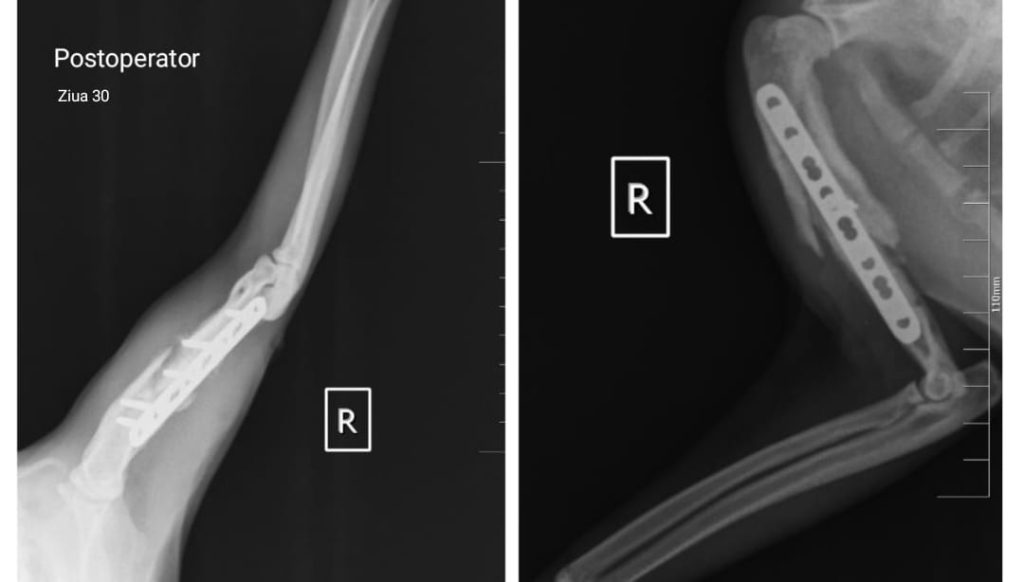

În cazul raselor de talie foarte mică, cunoscute drept “toy breeds”, fracturile de radius și ulnă constituie o categorie aparte de traumatisme ortopedice. Vascularizația redusă la acest nivel face ca aceste oase să fie vulnerabile chiar și în urma unor accidente minore – o săritură din brațele proprietarului sau de pe mobilier poate fi suficientă pentru a produce o fractură completă.

Tratamentul acestor leziuni este delicat, deoarece diametrul osos este extrem de redus, iar stabilizarea trebuie realizată cu maximă precizie. În prezent, dispunem de implanturi ortopedice de ultimă generație, concepute special pentru pacienții sub 2 kg, care permit stabilizarea sigură și eficientă a oricărui tip de fractură.

Pentru aceste rase, un pas esențial în managementul postoperator îl reprezintă extragerea implanturilor după confirmarea radiologică a vindecării osoase. Eliminarea acestora reduce riscul de resorbție osoasă și contribuie la menținerea unei integrității structurale optime pe termen lung.

Intervențiile sunt realizate cu anestezie inhalatorie și tehnici de blocaj loco-regional, ceea ce diminuează semnificativ nivelul de durere resimțită de pacient atât în timpul intervenției, cât și postoperator.

Astfel de situații demonstrează cât de mult contează echipamentele adecvate, experiența echipei și un protocol bine stabilit pentru a obține o recuperare completă și sigură.